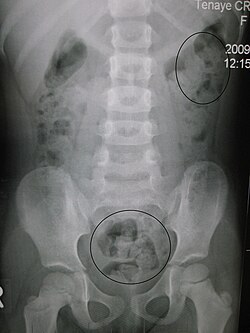

Ichakning turli qismlari oʻsma, bavosil tuguni bilan torayib qolganda, toʻgʻri ichakda axlat yigʻilganda ("axlat toshi") ham ich qotadi (mexanik Qabziyat). qabziyatning atonik va spastik (funksional) xili ham bor. Organizmning umumiy tonusi susayganda, yuqumli kasallik bilan ogʻrib, uzoq vaqt yotib qolganda, odamning qoni kamayib, ozib ketganda, deyarli qoldiq chiqarmay, yaxshi hazm boʻladigan yengil ovqat (qand, sutli ovqat, tuxum, goʻsht) isteʼmol qilinganda atonik qabziyat paydo boʻladi. Aqliy mehnat bilan shugʻullanib, kam harakat qilganda, ovqatlanish rejimi buzilganda atonik qabziyat koʻpincha odat tusiga kirib qoladi. Ichni boʻshatish ehtiyoji tugʻilganda boʻshanmasdan, istak qaytara berilganda ham qabziyat kuzatiladi. Hadeb klizma qilish va surgi dorilar ichaverish atonik qabziyatga sabab boʻladi.

Yashash sharoiti oʻzgartirilganda, safar-ga chiqqanda ham baʼzan qabziyat roʻy berishi mumkin.Ichakning turli qismlari oʻsma, bavosil tuguni bilan torayib qolganda, toʻgʻri ichakda axlat yigʻilganda („axlat toshi“) ham ich qotadi (mexanik qabziyat). Qabziyatning atonik va spastik (funksional) xili ham bor. Organizmning umumiy tonusi susayganda, yuqumli kasallik bilan ogʻrib, uzoq vaqt yotib qolganda, odamning qoni kamayib, ozib ketganda, deyarli qoldiq chiqarmay, yaxshi hazm boʻladigan engil ovqat (qand, sutli ovqat, tuxum, goʻsht) isteʼmol qilinganda atonik qabziyat paydo boʻladi. Aqliy mehnat bilan shugʻullanib, kam harakat qilganda, ovqatlanish rejimi buzilganda atonik qabziyat koʻpincha odat tusiga kirib qoladi. Ichni boʻshatish ehtiyoji tugʻilganda boʻshanmasdan, istak qaytara berilganda ham qabziyat kuzatiladi. Hadeb klizma qilish va surgi dorilar ichaverish atonik qabziyatga sabab boʻladi. Ichakning aylana muskullari uzoq tortishib qolganda (spazm) spastik qabziyat roʻy beradi. Vegetativ nerv sistemasining oʻta taʼsirlanishi (ruhiy kechinmalar va boshqalar) spazmga sabab boʻladi. Qoʻrgʻoshin, anilin boʻyogʻi, nikotin (chekish)dan surunkali zaharlanish natijasida paydo boʻladigan qabziyat ham spastik qabziyatga kiradi. Qabziyatda qorin ogʻir tuyuladi, tirsillab turadi, mijgʻib ogʻriydi, ishtaha boʻgʻiladi, ogʻiz bemaza boʻladi, bosh ogʻriydi, koʻngil gʻash boʻlib, ish qobiliyati pasayadi.